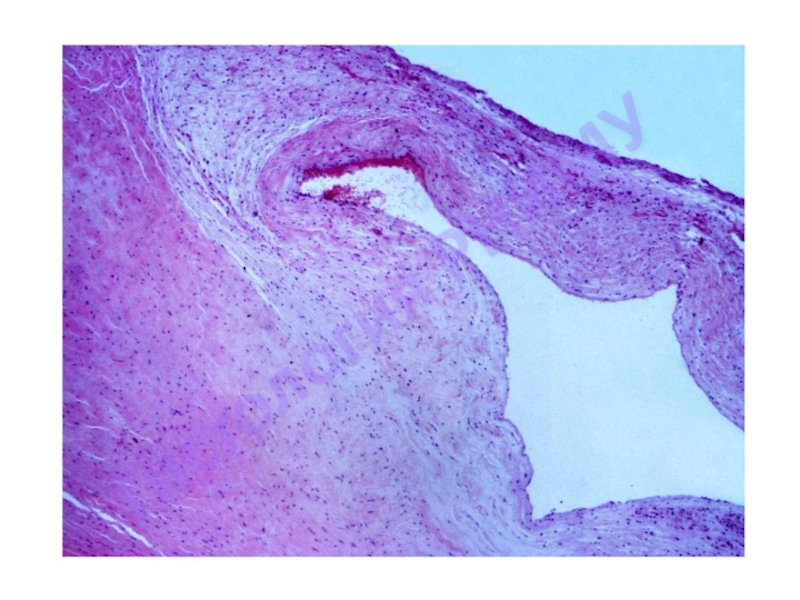

Слайд 4Общий принцип организации стенки кровеносного сосуда

1. Внутренняя оболочка

- Эндотелий

- Подэндотелиальный слой

- Внутренняя эластическая мембрана

2. Средняя оболочка

Гладкие миоциты, эластические волокна

- Наружная эластическая мембрана

3. Наружная оболочка (адвентициальная)

* В зависимости от принадлежности сосуда и его диаметра количество компонентов может меняться

Общий принцип организации стенки кровеносного сосуда1. Внутренняя оболочка				 - Эндотелий				 - Подэндотелиальный слой				 - Внутренняя эластическая мембрана2.